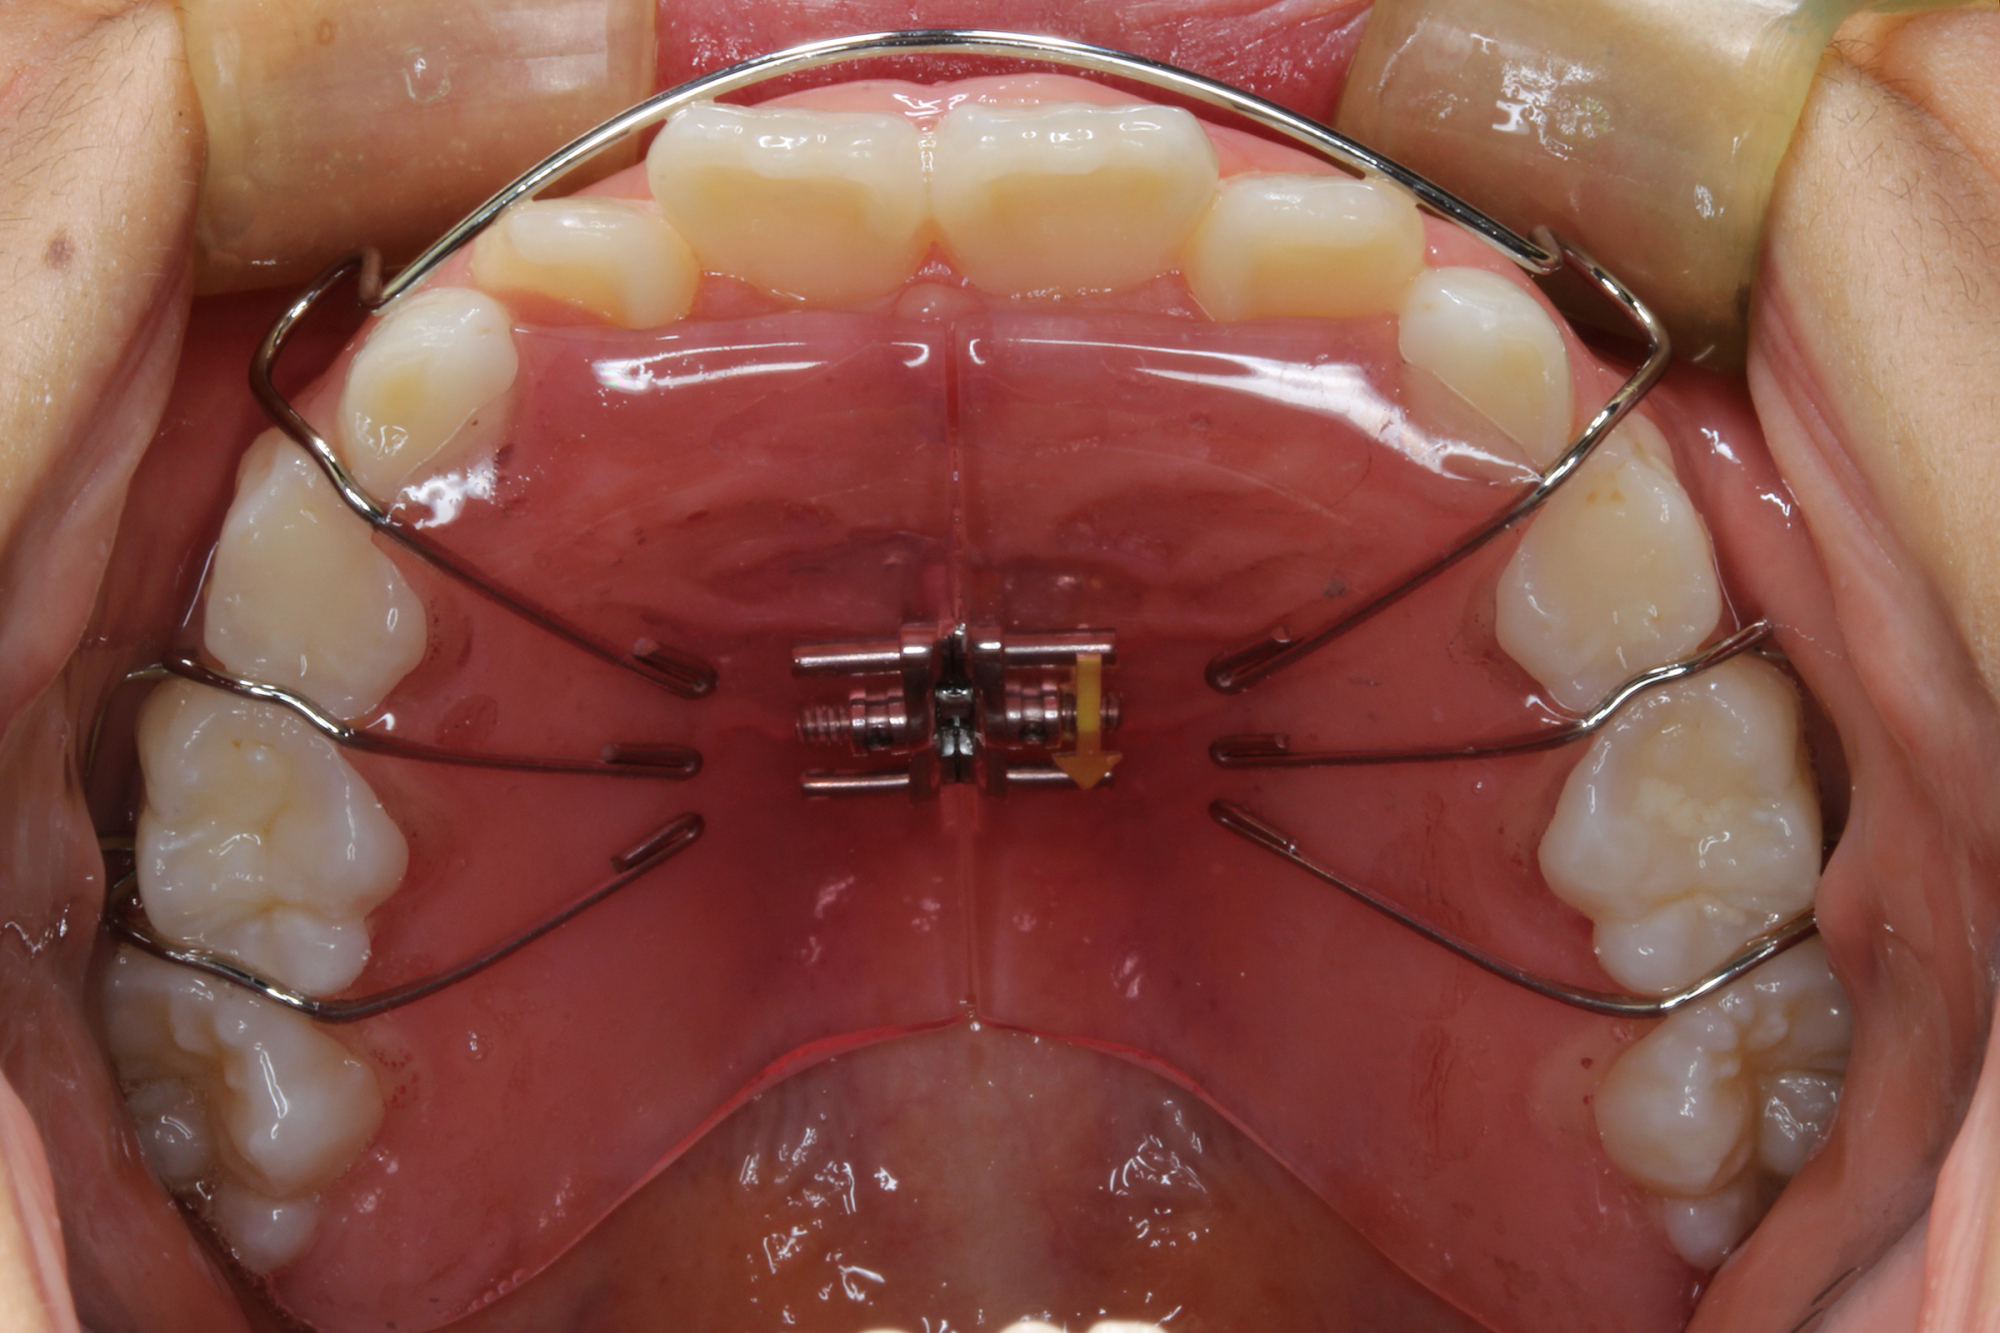

日本で行われている拡大床治療にも色々な方法がありますが当院での特長は最初に永久歯に生え替わる上下4本の前歯を奥歯の生え替わりが始まる前までに顎を拡大してきれいに並べることです。そのため拡大床治療の期間は小学校1年生頃から4、5年生頃までの間に限定しており、それまでに目的が達成できない場合には別の治療法に移行します。またゆっくりスペースを獲得するようにしているのも特長で2週間に1回ネジを回すようにしています。一般的には1週間にⅠ回ないし2回ネジを回すことが多いようです。ゆっくり進めるので一日の装着時間はお家にいるときと寝ている間だけにしています。学校や自宅以外での装着はせずゆっくり拡大していくので治療期間が長くなりますが後戻りは少なく確実になります。治療開始時期が大切ですので時期を逸した場合には拡大床治療は行いません。一般的に拡大床治療の評判が悪いのは開始時期が遅く、いつまでも治療を長引かせ治らないことによるものが多いようです。 拡大床治療はスペースを作って永久歯がならぶスペースを作ることが目標ですので細かい歯の向きや角度まで整えられないこともあります。そんな場合には別の矯正治療が必要になります。

拡大床治療で顎のスペースを拡げられるのは11歳くらいまでです。そのため個人差はありますが遅くても小学校2年生までに始めなければなりません。下の前歯が生え替わりはじめた頃から下の前歯が4本、上の前歯が2本生え替わる頃までが始め時です。すでに上下4本とも生え替わってしまった場合にはすでに遅いことが多くあります。